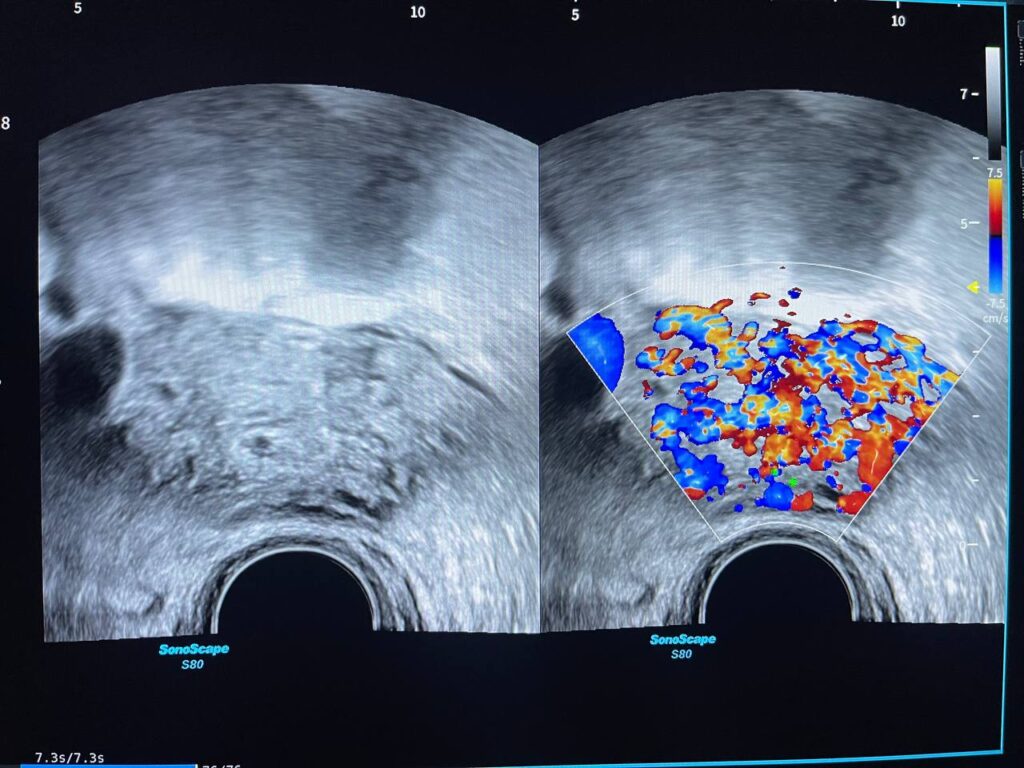

Presence of hyper vascular mass 47x31mm in the right cornua & within the interstitial layer , picture mostly of ectopic H Mole pregnancy , please for further study

Presence of hyper vascular mass 47x31mm in the right cornua & within the interstitial layer , picture mostly of ectopic H Mole pregnancy , please for further study